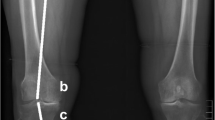

To derive BMD, grayscale Hounsfield units (HU) were converted to equivalent volumetric BMD (mg/cm3 K2HPO4) using subject-specific linear regression equations developed from known densities ranging from − 50 to 375 mg/cm3 K2HPO4 within the QCT phantom included in each individual axial image (r 2 > 0.99) [28] and interpolation to determine equivalent volumetric BMD values. Higher density values were linearly extrapolated (Fig. 1a). Subject-specific half maximum height thresholds [29] were then determined to define the proximal tibial subchondral and cortical surfaces. Two 3D image volumes were built, one including the entire proximal tibia as previously described [13, 28] and another by segmenting individual serial images using semi-automatic region growing and manual correction at the epiphyseal line (Fig. 1b). Both sets of imaged volumes were segmented using commercial software (Analyze10.0; Mayo Foundation, Rochester, MN, USA) and an interactive touch-screen tablet (Cintiq 21UX; Wacom, Krefeld, Germany). Imaged volumes were reoriented to a neutral position where medial and lateral plateaus were approximately parallel. We then divided the imaged volumes into medial and lateral compartments, measured by using 40% of the maximum medial-lateral axis of each respective side [16] (Fig. 1c).

Methodological process consists of converting computed tomography (CT) grayscale intensities to bone mineral density (BMD) using a quantitative CT (QCT) reference phantom (a), followed by building two imaged volumes for each tibia, one with manual correction at the epiphyseal line and one using the full tibia (b). Imaged volumes were divided into lateral and medial regions (c) and then the outer 2.5-mm and subchondral 7.5-mm depth were removed from each imaged volume (d). BMD measurements included epiphyseal BMD between the epiphyseal line and 7.5 mm from the subchondral surface and metaphyseal BMD 10 mm distal from the epiphyseal line (e)

To ensure that trabecular BMD measurements did not include cysts (which would lead to arbitrarily low measures of BMD) [13, 30] or peripheral high-density cortical bone, the most proximal 7.5-mm region (relative to the subchondral surface) was removed from the segmentations (Fig. 1d), as was 2.5 mm of peripheral cortical bone (Fig. 1d). The 7.5-mm depth was based upon observed cyst locations from our earlier work [13, 30] and work by Chiba et al. [31], which limited depth analyses to 5 mm from the subchondral surface. In extreme cases, large cysts extended from the subchondral cortical region (0 − 2.5 mm) through the subchondral trabecular region (2.5–5 mm) and occasionally into depths greater than 5 mm from the subchondral surface. By using a conservative 7.5-mm depth from the subchondral surface, we ensured the exclusion of large cysts from our analysis. Following material removal, we measured epiphyseal trabecular BMD from the 7.5-mm depth to the epiphyseal line (Fig. 1e), which was located approximately 15 mm from the subchondral surface. Metaphyseal trabecular BMD was measured 10 mm distal to the epiphyseal line (Fig. 1e).